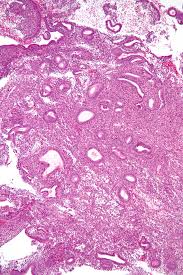

129_236__cuprins conținutul administrarea radiațiilor ionizante în regiunea pelvină pentru alte tipuri de boli neoplazice administrarea îndelungată de tamoxifen tratament cu hormoni estrogeni fără compensare de progesteron. If pedunculated, they can protrude through the cervix into the vagina. Qualität & sicherheit aus deutschland. Proliferation of benign endometrial stromal and glandular elements, protruding into the endometrial cavity. During a d&c, your healthcare provider will remove tissue from your uterus. Estrogen has a major role in the thickening of the endometrium so it has been linked to the growth of uterine polyps 2, 3, 5. Post partum z39.0 post sc z39.0 Stasis dermatitis refers to the pores and skin. If it does not go away, causes discomfort, or gets larger, it may need to be removed. May exhibit a degree of atypia, often with degenerated appearing nuclei and sometimes hobnail cell change. Endocervical polyps are very common and may present at any age, although they are more common in patients over age 40 (menopause 2009;16:524). Daftar kode icd tersering revisi. Papillary proliferations with fibrovascular cores occasionally occur on the surface of an endometrial polyp or within cystically dilated glands.